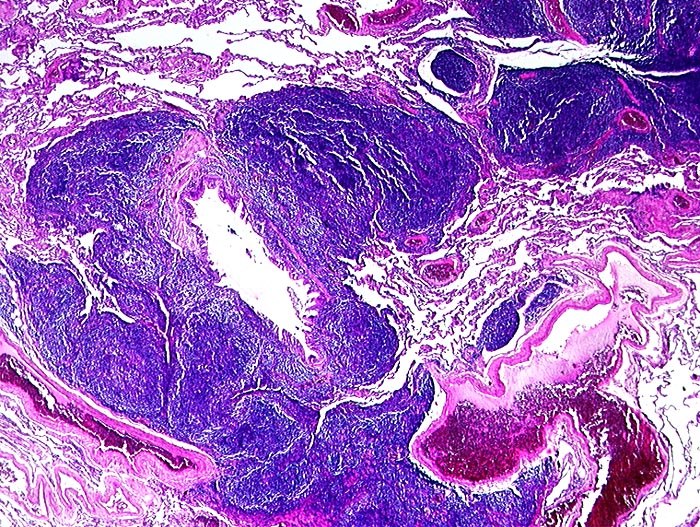

Marginalzonenlymphom: extranodal vom MALT Typ

Lunge

Dichtes Lymphominfiltrat entlang der Lymphspalten um einen Bronchiolus.

Hier: Kleinerer Herd hilusnah entlang Lymphgefässspalten (makroskopisch wie Lymphangiosis carcinomatosa imponierend). Grösserer Herd subpleural 2.4cm Durchmesser. Hiluslymphknoten nicht befallen. Stadium IE.

Verdacht auf peripheres Lungenkarzinom. Peripherer Rundherd als einzige Tumormanifestation im CT.

Altersgipfel pulmonaler MALT Lymphome 6.-7. Dekade. Meist solitärer Rundherd, weniger häufig multinodulärer Befall und Pleuraerguss. Bei der Mehrzahl Stadium IE initial. Sehr indolenter Verlauf mit günstigster Prognose aller extranodalen Marginalzonen Lymphome.